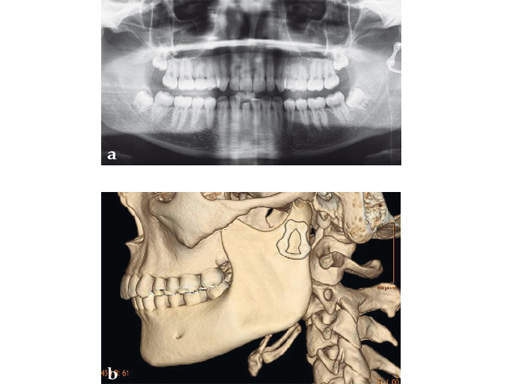

Case 3

Case provided by Carl-Peter Cornelius, Mnchen, Germany